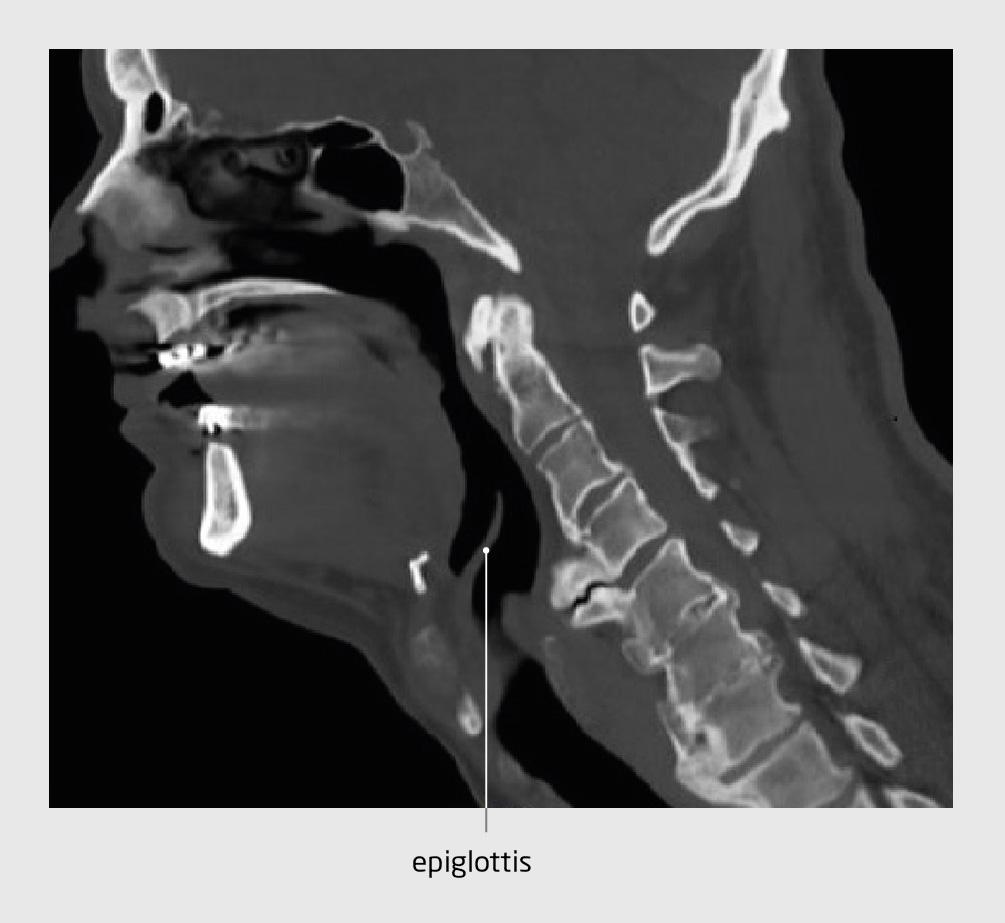

Bij lichamelijk onderzoek zagen wij een harde zwelling aan de rechter voorzijde van de nek van patiënt. Een CT-scan van de cervicale wervelkolom, die al was verricht, liet aan de ventrale zijde uitstulpende osteofyten zien (figuur 2). Vanwege de progressieve mechanische passageklachten besloten wij om de cervicale osteofyten operatief te verwijderen.